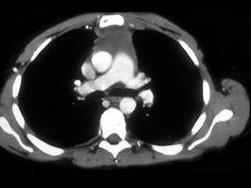

问题 男,64岁,胸部隐痛伴眼睑下垂2个月余,请结合影像学检查图,选出最可能的诊断 ( )

选项 A、纵隔畸胎瘤 B、间皮囊肿 C、胸腺瘤 D、胸内甲状腺肿 E、淋巴瘤

答案 C